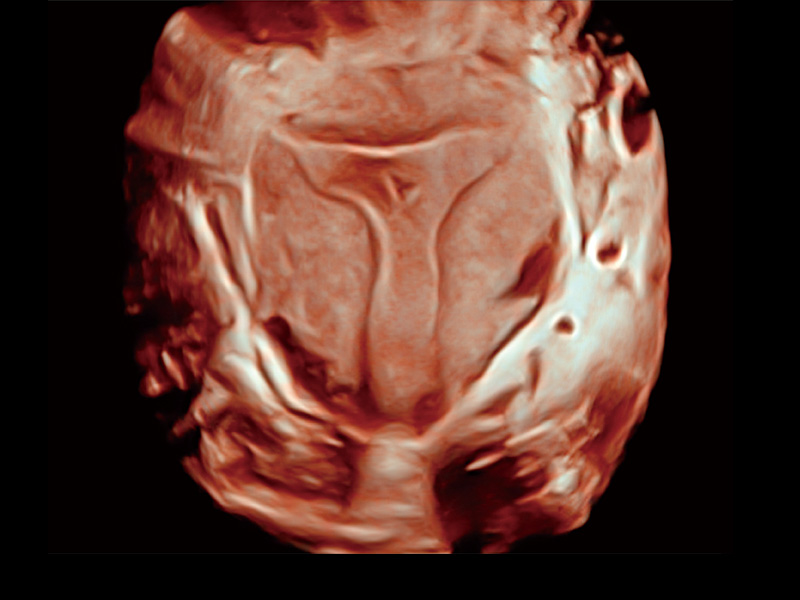

“生育问题”即关系民族复兴,也关系亿万家庭的幸福。随着婚育年龄推迟、社会压力增加等因素,越来越多人群也面临着“生不出、生不好”的问题。辅助生殖作为治疗不孕不育最有效的方法之一,也逐渐成为育儿新希望。而超声检查能为生殖需求人群的初诊评估提供宝贵的信息。 P20 Elite是狗万官方网站匠心打造的一款生殖应用型彩超。她继承狗万官方网站高端极光平台,突破性地将多款新型芯片及硬件模块进行整合,均衡了高端系统性能与小巧灵动机身。P20 Elite卓越的图像质量搭载专科探头,旨在为您提供全面的辅助生殖解决方案。

P20 Elite配备了丰富的生殖探头群和临床应用功能,在卵泡监测、穿刺取卵、胚胎移植、妊娠确认等领域,为生殖需求人群提供了新的临床机会,重新定义高端超声如何应用于生殖健康检查。